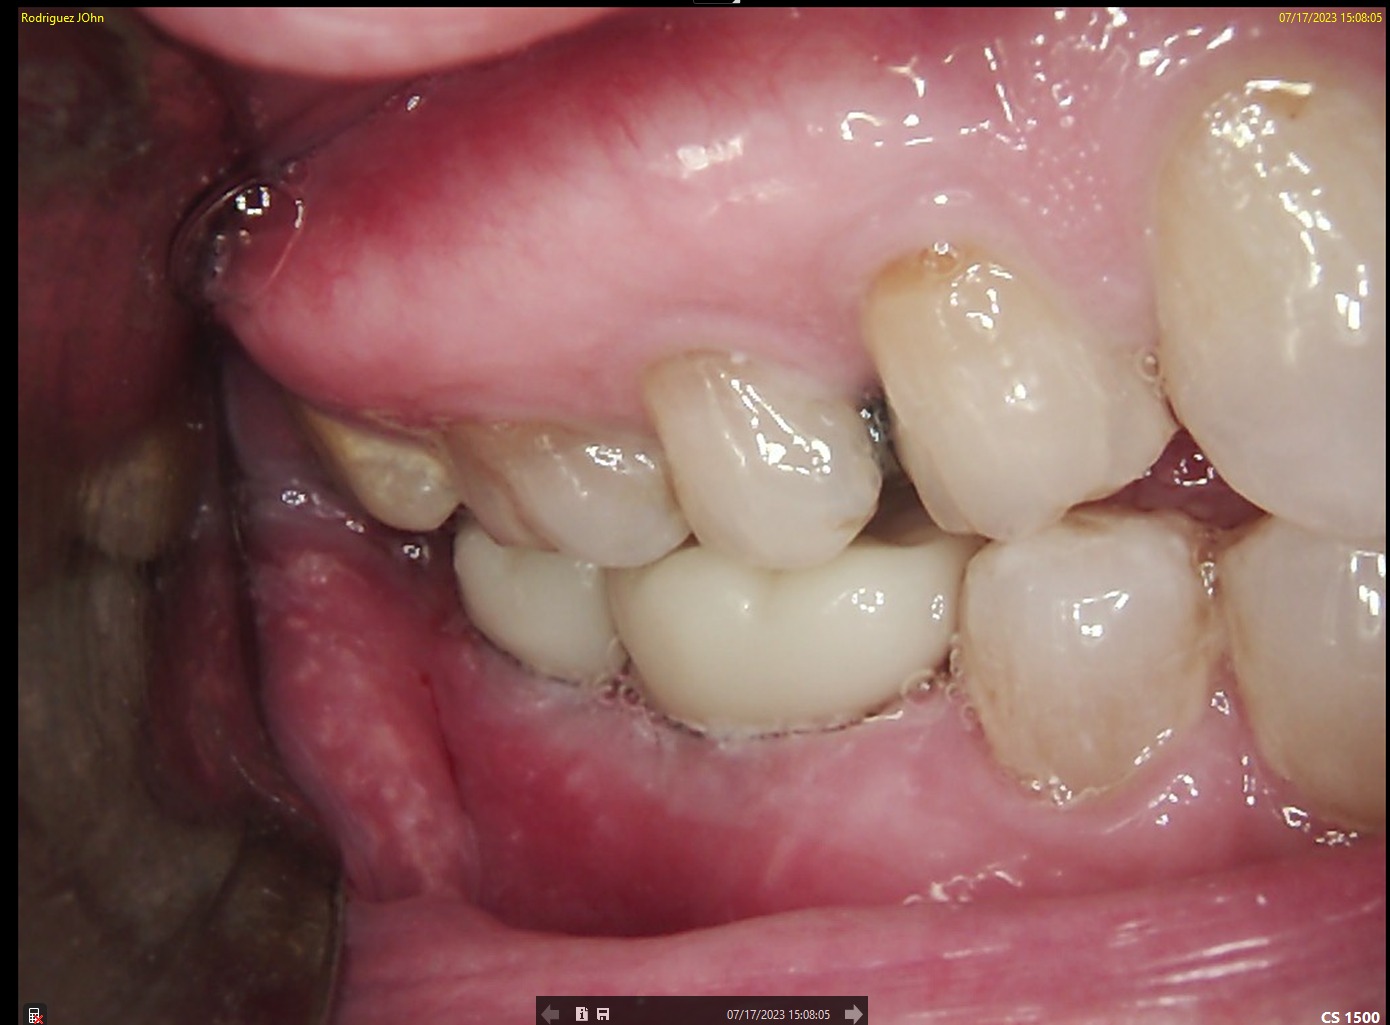

FINAL RESTORATION

Final restorations demonstrated:

• Proper occlusal integration

• Natural emergence profile

• Radiographic confirmation of stable crestal bone levels

Clinical and radiographic images confirmed successful functional and esthetic outcomes at delivery.

FOLLOW-UP - 2024

One-year follow-up evaluation showed:

• Stable peri-implant soft tissue contours

• Absence of inflammation or recession

• Radiographically preserved crestal bone levels

The implants remained fully functional with excellent tissue response.